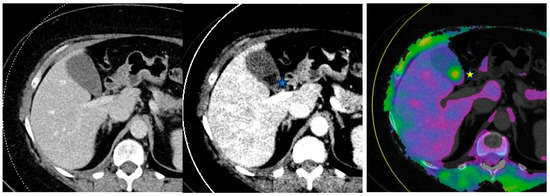

5.9. Oncology Examples